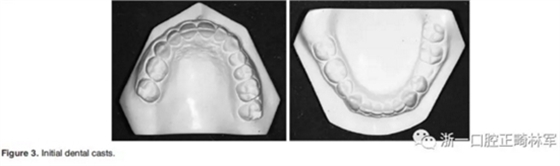

3.體格檢查:直面型,露齦笑,深覆合、合平面傾斜(Figure 1)。上中線偏右3mm,下中線偏左2mm。磨牙II類關(guān)系,左側(cè)尖牙II類關(guān)系,右側(cè)尖牙I類關(guān)系,左下第二磨牙低位咬合,右上前磨牙缺失。覆蓋率為100%,覆蓋度為4mm。咬合平面重度傾斜,左側(cè)向下移位(Figure 2、3)。